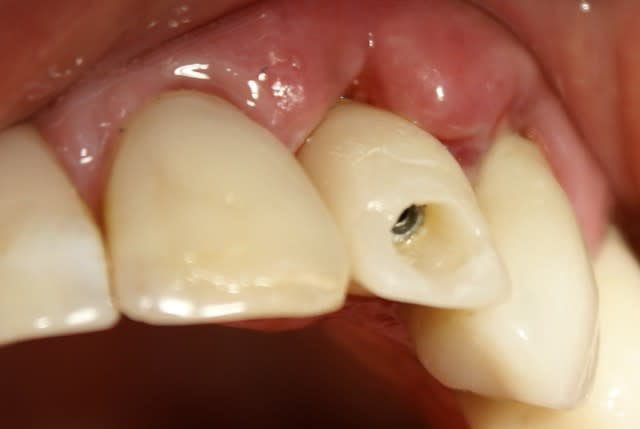

Tout à fait d'accord growler et c'est d'ailleurs ce que l'on peut voir sur le cas suivant. Fracture radiculaire, aucune infection periradicualire. Extraction et implantation immediate. Espace existant entre l'implant et l'alvéole est comblé par du BioOss. Un logement sous gingival est formé en vestibulaire et palatin de facon à pouvoir recouvrir le tout par BioGide et un conjonctif enfoui.

L'implant est de 15mm mais l'alvéole était large et 50% environ de la surface implantaire n'était en contact qu'avec du BioOss. J'ai pour cela préféré enfouir.

Petite question dentiste 57 : il semblerait dans le 2eme cas que tu présentes que tu ne recouvres pas ton implant par la membrane (qui pourrait comme l'a dit Amibien être poinconnée pour laisser passer ton pilier). Si c'est bien le cas peux tu m'expliquer pourquoi ? Quel est le risque à ton sens que ton comblement palatin et vestibulaire se fasse la malle par le "sulcus" entourant ton implant ?